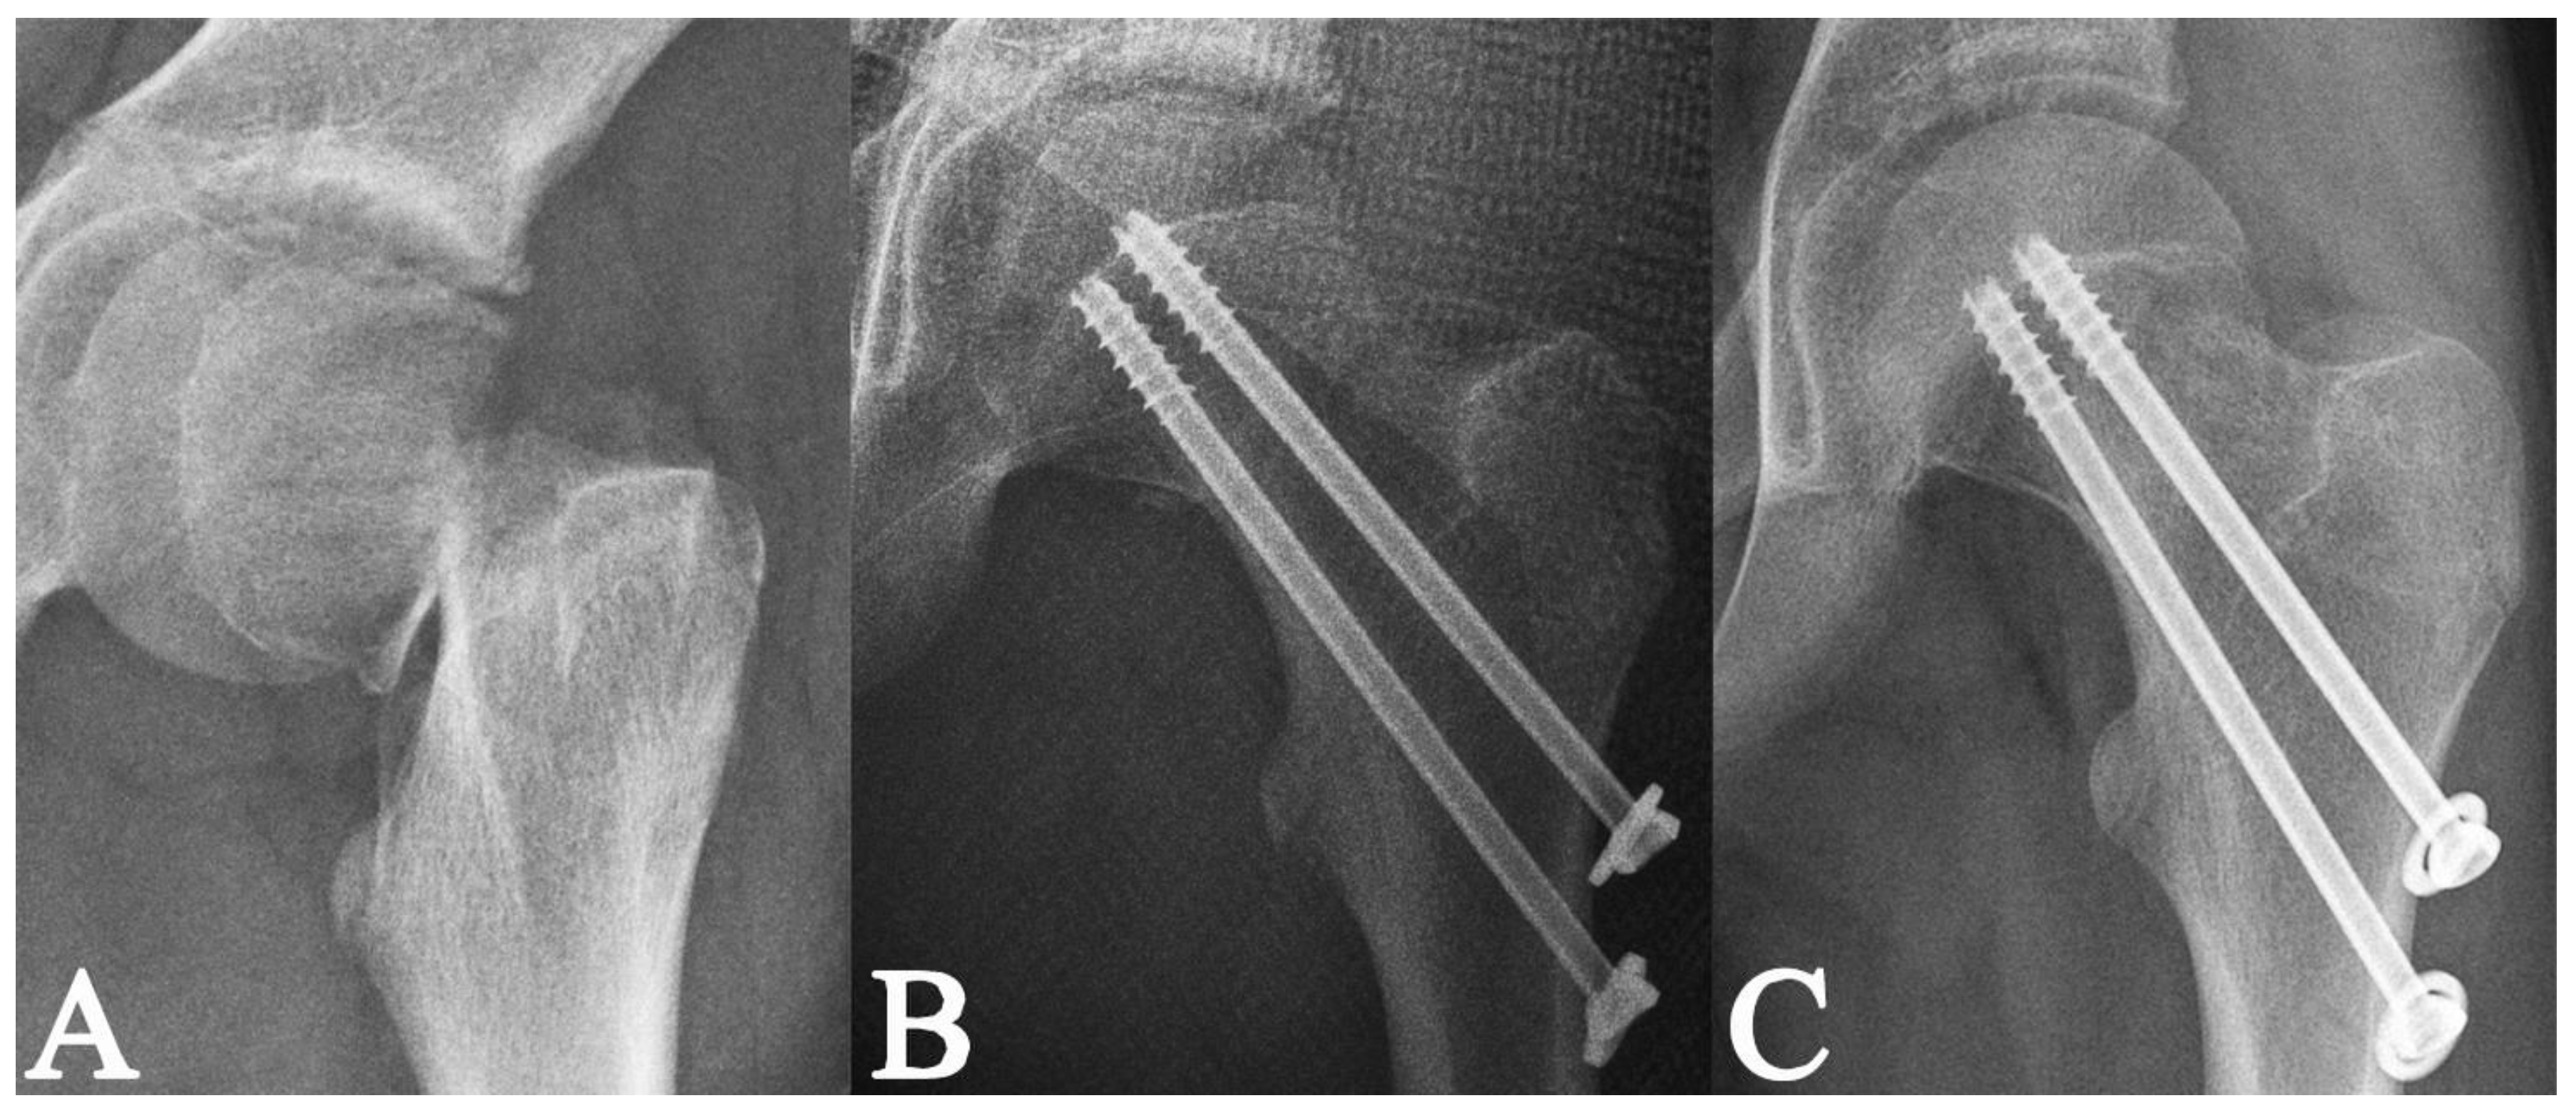

| Fixation method | Two cannulated screws (n = 100; 75.8%) | 3.1 ± 1.6 | 0.919 | 0.360 |

| Three cannulated screws (n = 32; 24.2%) | 3.4 ± 1.5 | |||